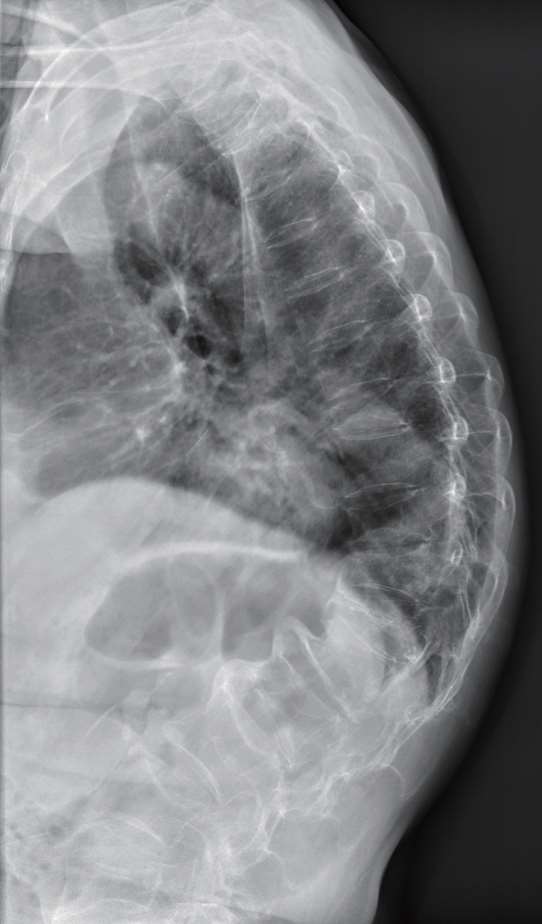

弯腰驼背也是导致椎体骨折的常见原因之一。最初的微小骨折会引起疼痛,随着时间的推移,这些微骨折会不断加剧,最终导致椎体发生可能缓慢发展的压缩性骨折(见图1-5)。多个椎体前端塌陷,导致脊柱弯曲畸形,最终形成驼背。

图1-5 压缩性骨折(胸腰椎侧位X光片)

注:患者为70岁女性,因为双侧背部疼痛一周到医院就诊,拍片提示胸椎、腰椎多个椎体出现了压缩性骨折,整个脊柱后凸变形。